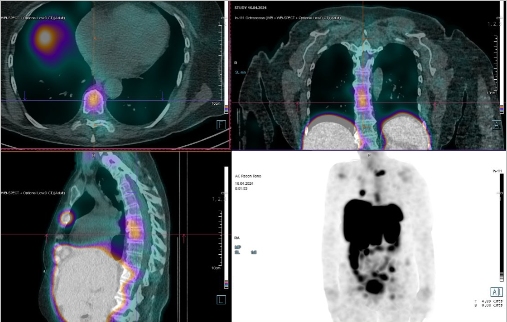

Scintigrafie Octreoscanem

I. v. jsme aplikovali 190 MBq analogu somatostatinu značeného 111In

(přípravek OctreoScan firmy Curium Netherlands B.V.) a provedli pomocí hybridní tomografické scintilační kamery Symbia T2 firmy Siemens opatřené kolimátory pro střední energie planární celotělovou scintigrafii a cílenou tomografickou scintigrafii (SPECT) břicha a pánve kombinovanou s CT.

/ Obr. č. 1: Celotělová scintigrafie v přední a zadní projekci 4 (vlevo) a 24 hod. (vpravo) po aplikaci OctreoScanu.

/

/ Obr. č.

2: Celotělová scintigrafie a fúze SPECT/CT 4 hod. po aplikaci OctreoScanu. Zaměřeno na pravý jaterní lalok s ložiskem.

Pozorujeme patologické ložisko zvýšené depozice radiofarmaka v segmentu S4 pravého jaterního laloku, ve dvou uzlinách – jedné nad bránicí a druhé pod levým jaterním lalokem a v pánvi na rozhraní levé kosti kyčelní a kosti křížové, nález svědčí pro tkáň se zvýšenou denzitou somatostatinových receptorů.

Závěr:

U 68leté ženy s neuroendokrinním tumorem nejasného primárního zdroje prokazujeme generalizaci v játrech, uzlinách a skeletu.